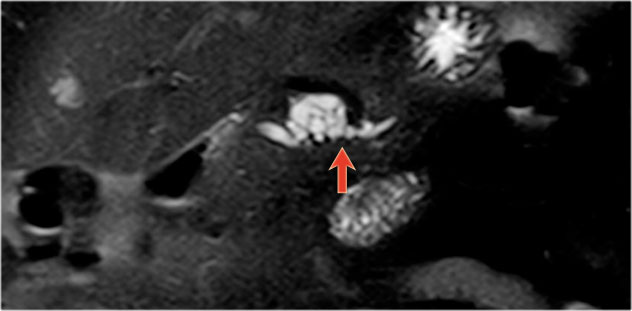

In a 73 year old male a hypoechoic lesion was found in the pancreatic body, that looked like a cystic lesion.

CT also identifies the lesion but isn't of much help.

Continue with the MRI.

The heavily T2WI nicely demonstrates the multicystic lesion with the connection to the pancreatic duct.

This was diagnosed as a branch-duct IPMN.